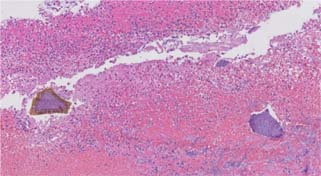

Figure 4: Medium power image of fibrinopurulent exudate and Kayexalate crystal (Hematoxylin and eosin, 10× magnification).

Figure 5: Medium power image of fibrinopurulent exudate, with sevelamer (left) and Kayexalate (right) crystals (Hematoxylin and eosin, 10× magnification).